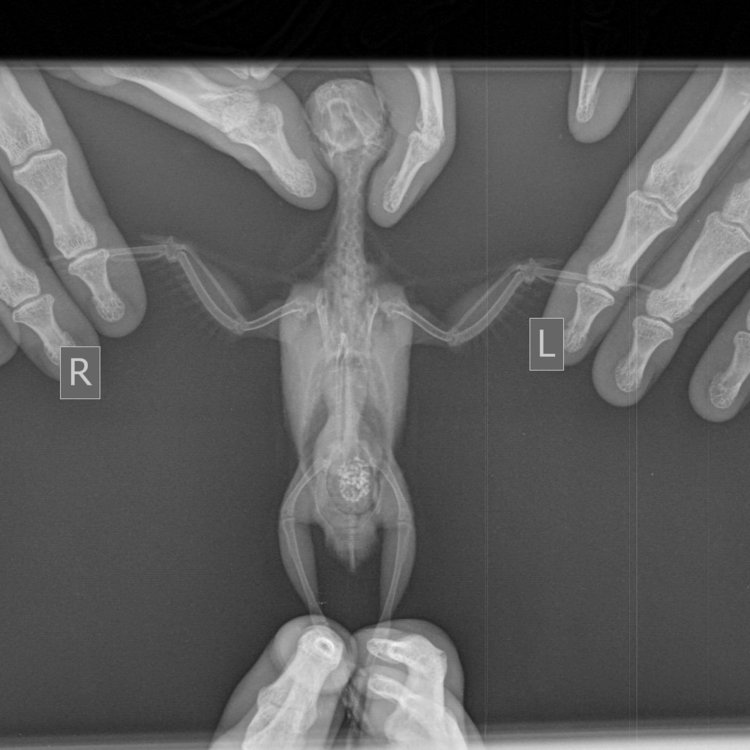

все про ренген -см у меня в подписи -нужно обязательно ПРАИВЛЬНО разложить птицу на столе иначе НЕТ смысла его вообще делать. Снимок нужен на боку и на спине.

Отказ лапы\лап - если НЕТ ФИЗ ТРАВМЫ и если мажем травмагелем\даем травматин и нет рез-та неделями - то обычно предпологаем опухоль\почки, поэтому РЕНГЕН нужен.

Сделали рентген, на спине, слева и справа. Делали в нескольких вариантах, выкладываю все:

Мягкие ткани Мелкий _ 10 kg-Груд. клетка  LAT-07.07.2018-12_56_27-801.JPEG

Мягкие ткани Мелкий _ 10 kg-Груд. клетка  LAT-07.07.2018-12_57_50-762.JPEG

Мягкие ткани Мелкий _ 10 kg-Груд. клетка  LAT-07.07.2018-12_57_51-635.JPEG

Мягкие ткани Мелкий _ 10 kg-Груд. клетка  LAT-07.07.2018-12_57_52-509.JPEG

Мягкие ткани Мелкий _ 10 kg-Груд. клетка  LAT-07.07.2018-12_59_20-415.JPEG

Мягкие ткани Мелкий _ 10 kg-Груд. клетка  LAT-07.07.2018-12_59_21-273.JPEG

Мягкие ткани Мелкий _ 10 kg-Груд. клетка  LAT-07.07.2018-12_59_22-162.JPEG

Мягкие ткани Мелкий _ 10 kg-Груд. клетка  LAT-07.07.2018-13_00_33-844.JPEG

Мягкие ткани Мелкий _ 10 kg-Груд. клетка  LAT-07.07.2018-13_00_34-718.JPEG

Мягкие ткани Мелкий _ 10 kg-Груд. клетка  LAT-07.07.2018-13_00_35-591.JPEG